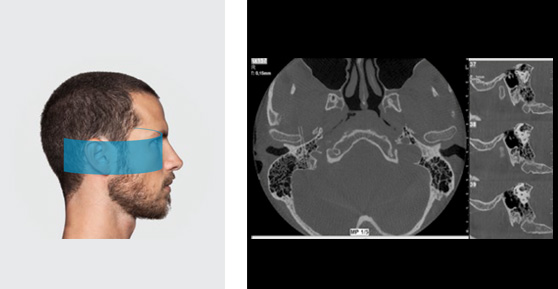

FOV 7 X 6 см

Изображение высокого разрешения как внутреннего уха, так и каменистой кости для точного диагноза или постоперационного контроля. Подходит для позиционирования кохлеарного имплантата.